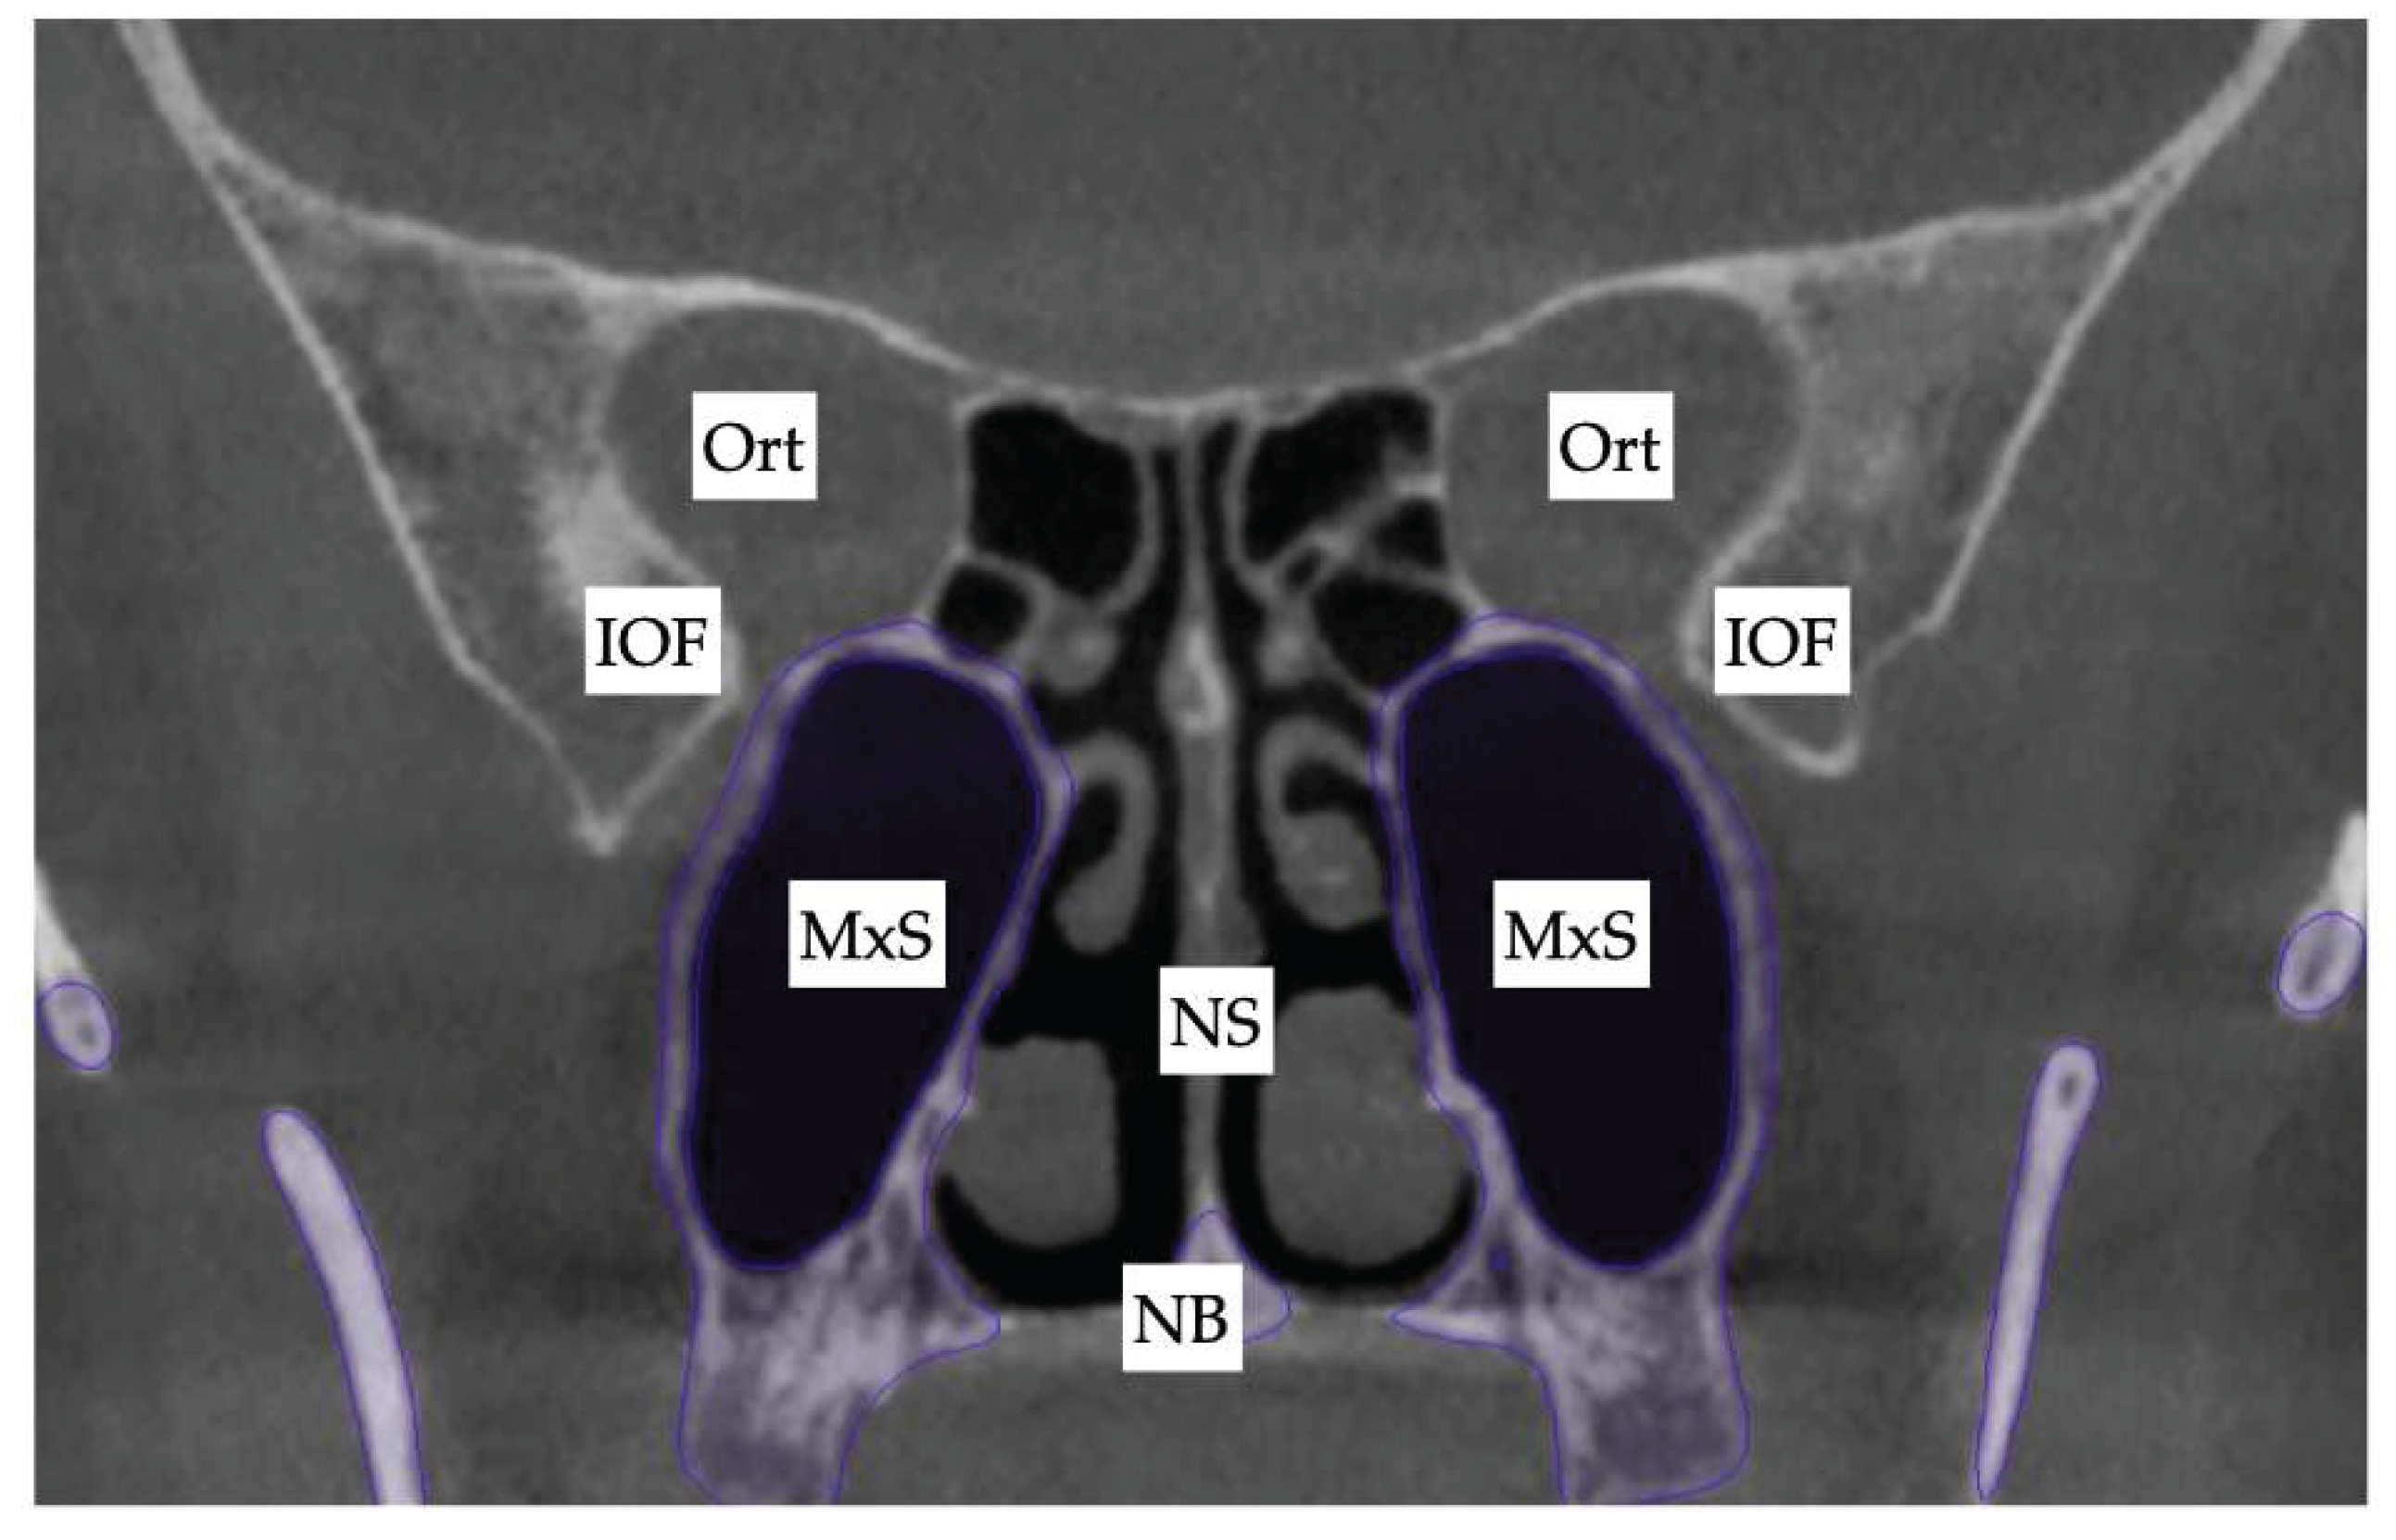

Background: While mini-screw-assisted rapid palatal expansion (MARPE) is effective for correcting maxillary transverse deficiency in adults, perimaxillary suture disarticulation—particularly at the pterygomaxillary junction—can be inconsistent. This study evaluates skeletal and dentoalveolar outcomes of a novel 3D-guided midpalatal piezocorticotomy-assisted MARPE protocol, focusing on expansion symmetry and pre-existing asymmetries. Methods: Three adult patients were retrospectively analyzed after treatment with 3D-guided midpalatal piezocorticotomy-assisted MARPE expansion and one with non-guided midpapalatal piezocorticotomy and MARPE expansion. Surgical guides were digitally designed using CBCT data to align with the nasal septum orientation in multiple planes. Perimaxillary suture disarticulation was measured pre- and post-expansion, and dentoalveolar changes were evaluated. Post-expansion asymmetries were addressed using directly printed aligners. Results: Complete midpalatal suture separation (mean 8.48 mm), involving both anterior and posterior nasal spine regions, was achieved in one patient. Bilateral pterygomaxillary disarticulation averaged 1.06–1.23 mm, resulting in forward–outward rotation of the nasomaxillary complex. Additional separation occurred at the frontonasal (2.03 mm) and vomeromaxillary (1–2 mm) sutures, with no significant changes in orbital or peri-orbital sutures. One patient presented with pre-existing dentoalveolar asymmetry, which intensified the perceived post-expansion imbalance but was successfully corrected with directly printed aligners. In the second case, 5.6 mm of suture separation resulted in a limited lateral nasal width increase (<1.5 mm), while maxillary base expansion exceeded 6 mm. A significant canine plane cant (1.2 mm) and divergent axial inclinations of the maxillary central incisors relative to the palatal plane were also observed. In the second case, a non-impactful palatal bone fracture with asymmetric displacement of the left palatine fragment was documented. After 16 months of aligner therapy, all cases exhibited favorable remodeling of the palatal structures, midpalatal suture, and alveolar processes, accompanied by improved dental alignment, occlusal plane symmetry, and mandibular dentoalveolar adaptation. The dento-alveolar expansion achieved in the third case over the course of 16 months of treatment was approximated at 4 mm. The fourth case showed consistent improvement with direct printed aligners after MARPE midpalatal diasrticulation of 11 mm after experiencing minor bone fracture. Conclusions: Human skulls exhibit considerable variability between the left and right sides, which can influence spatial balance. Pre-existing cranial asymmetries appear to be the primary contributors to asymmetry following MARPE treatment. Careful evaluation of dentoalveolar discrepancies and axial tooth inclinations is essential for preventing and managing potential asymmetric dental arch outcomes during the post-expansion phase. Although peri-maxillary bone fractures are relatively uncommon, their occurrence is influenced by multiple factors. Adjunctive techniques, such as 3D-guided midpalatal piezocorticotomy, show promise in significantly lowering the risk of intra-expansion peri-maxillary fractures.

| Suture nomenclature | Associated anatomical structure | Paired/Single |

|---|---|---|

| Midpalatal | Hard palate | Single |

| Palatinomaxillary | Hard palate | Paired |

| Nasomaxillary | Bridge of the nose | Paired |

| Zygomaticomaxillary | Zygomatic arch | Paired |

| Lacrimomaxillary | Floor of the Orbit | Paired |

| Ethmoidomaxillary | Floor of the Orbit | Paired |

| Sphenomaxillary | Floor of the Orbit | Paired |

| Vomeromaxillary | Nasal septum | Paired |

| Frontomaxillary | Bridge of the nose | Paired |

| Pterygomaxillary | Maxillary sinus wall | Paired |